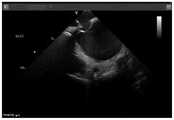

图7是示例房间隔穿刺鞘组合在下拉过程中的右房压迹;Figure 7 is a right atrial impression during pull-down of an example transseptal sheath combination;

④保持超声导管上腔静脉扇面不动,逐渐往下回撤房间隔穿刺鞘组合,在回撤过程中超声导管手柄逐渐松R弯,实时跟踪房间隔穿刺鞘组合的位置。(图7)④Keep the fan of the superior vena cava of the ultrasound catheter still, and gradually withdraw the atrial septal puncture sheath combination. During the withdrawal process, the ultrasonic catheter handle gradually loosens the R-bend, and the position of the atrial septal puncture sheath combination is tracked in real time. (Figure 7)